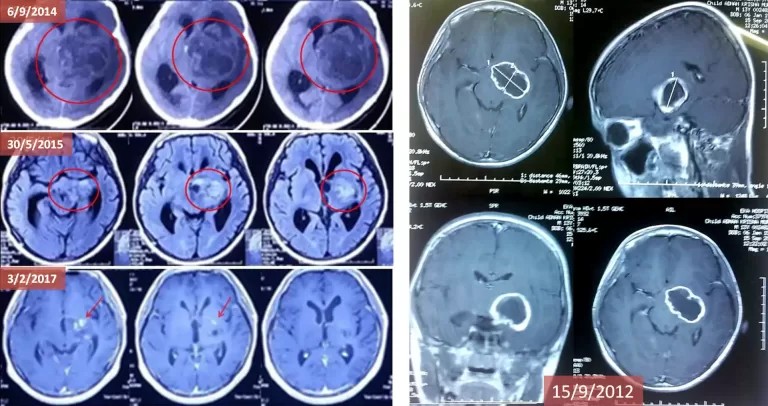

Deep in the Nerve Center: Defying an Inoperable Death Sentence

Surpassing a Decade of Survival Without Surgery or Chemotherapy

In 2012, 12-year-old Adnan was diagnosed with a malignant tumor in the basal ganglia—the brain’s critical coordination center. The tumor pressed against the mesencephalon, causing severe headaches and loss of vision, hearing, and motor skills. Due to its perilous location, doctors deemed the cancer inoperable, as surgery or radiation would risk fatal nerve damage. With no other options, his father turned to ECCT. Although he experienced a setback after stopping treatment prematurely, re-commencing with a redesigned helmet successfully shrank the massive 10cm tumor and reduced his hydrocephalus. Ten years later, Adnan remains healthy and pain-free, communicating via technology and living a life that was once considered impossible.